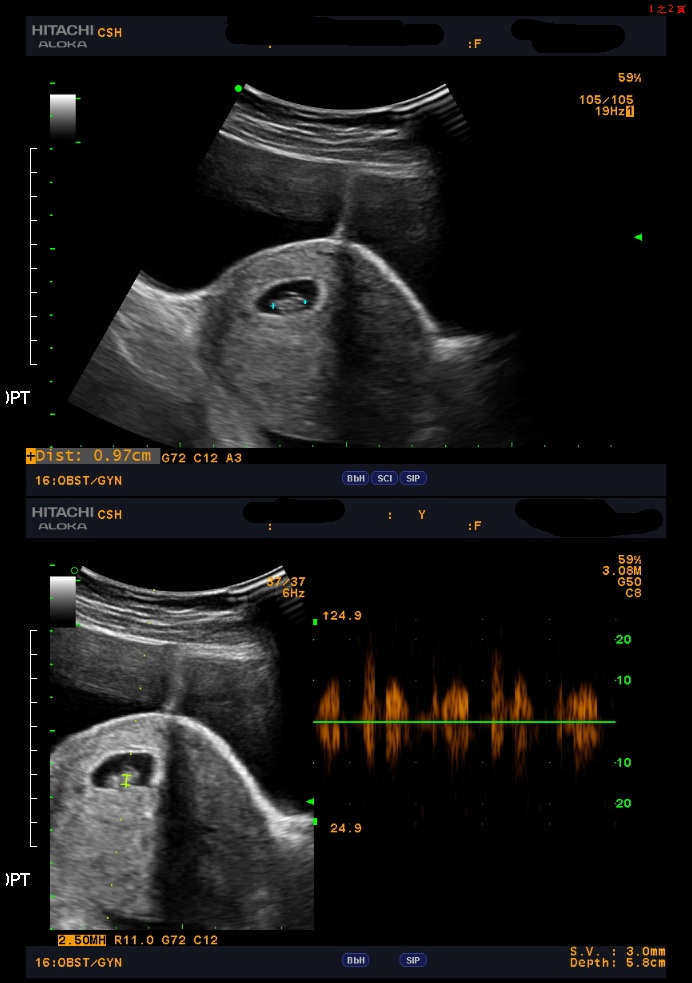

一位三十出頭的女性卵巢功能良好(AMH 1.8),而先生的精蟲數偏低、活動力不足。多家診所建議直接進行試管嬰兒療程,但夫妻雙方希望先嘗試其他方式。

在初診檢查評估過程中,我們透過精液分析進一步檢視了精蟲活動力與形態比例,報告顯示先生的活力精蟲總數約五百萬上下,其實仍然具備人工受孕(IUI)的標準條件,因此也符合夫妻雙方希望先嘗試其他療程的方式,以人工受孕療程為優先考量,不立即進入試管嬰兒階段。

本次療程採用了新一代精蟲分離技術,利用精蟲往上流動,經由特殊薄膜模擬精蟲在自然環境中的游動過程,能有效挑選出活動力佳且 DNA 結構完整的健康精蟲,以提升受精率與胚胎品質。

新一代精蟲分離技術相較於傳統離心法,新一代精蟲分離技術可降低精蟲受損風險並且提高樣本品質,臨床統計顯示人工受孕成功率平均可增加約三倍。該對夫妻在接受治療後,於第一次人工受孕即成功懷孕,最終順利誕下一名健康新生兒。